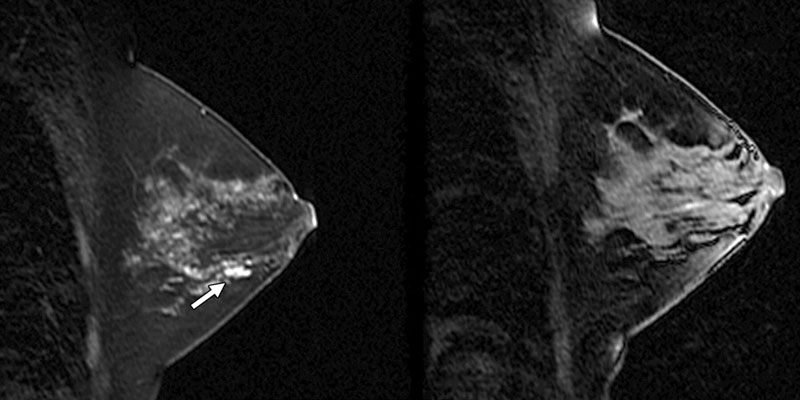

- ультразвуковое исследование (УЗИ) – во время его проведения оцениваются размеры и локализация объемного новообразования, особенности его тканевого строения, наличие или отсутствие в нем вторичных патологических процессов. Также для исключения злокачественного процесса исследуются регионарные лимфоузлы;

- компьютерная томография (КТ) – при помощи компьютерных срезов оценивают особенности железистой ткани дополнительной молочной железы, а также проводят дифференциальную диагностику с опухолями (в том числе изучают состояние регионарных лимфатических узлов);

- магнитно-резонансная томография (МРТ) – возможности те же, что и КТ;